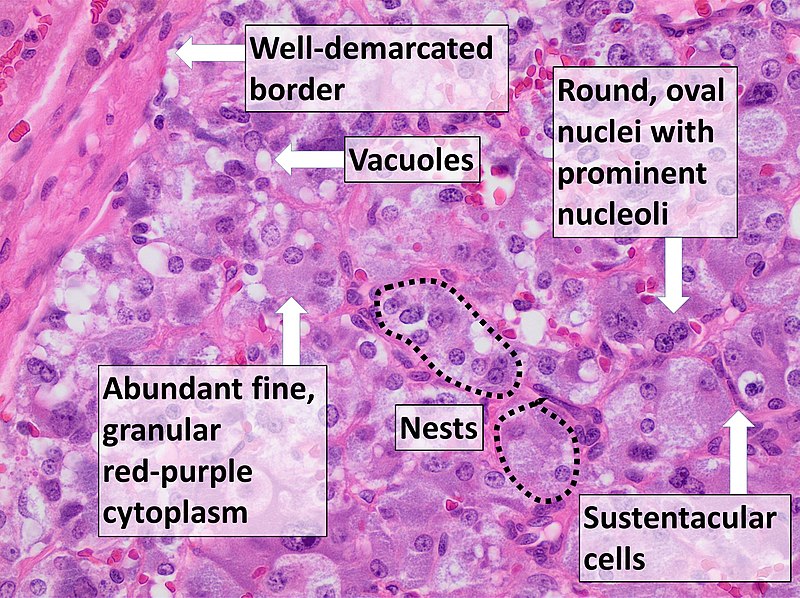

Pheochromocytoma

A particular kind of neuroendocrine tumor (NET) known as a pheochromocytoma develops from chromaffin cells.

Chromaffin cells are located in the adrenal glands and create hormones that the body requires.

Clinical features of pheochromocytoma results from elevated serum catecholamine levels.

Clinical features of pheochromocytoma include:

- Perspiration

- Tachycardia

- Palpitations

- Headaches

- Episodic hypertension

Increased 24-hour urine production and serum metanephrine levels are used to diagnose the disease.

Medical excision is used as a treatment of choice.

When the tumor is manipulated, catecholamines may leak into the bloodstream.

An irreversible alpha-blocker called phenylbenzylamine is given preoperatively to stop a hypertensive crisis.

Pheochromcytomas often follows the rule of 10s:

- 10% bilateral

- 10% familial

- 10% malignant

- 10% located outside of the adrenal medulla such as bladder wall or organ of Zuckerkandl at the inferior mesenteric artery root

Pheochromocytoma is associated with other medical conditions such as:

- Von Hippel-Lindau disease

- Neurofibromatosis type 1 (NF1)

- Multiple endocrine neoplasia (MEN) types 2A and 2B (MEN 2A and MEN 2B)